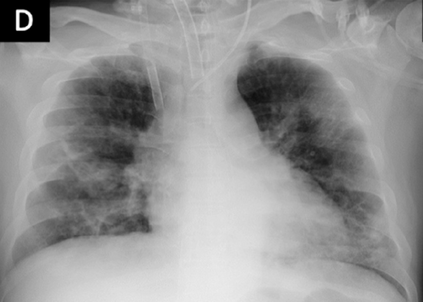

Across the world's coronavirus disease 2019 (COVID-19) hot spots, the need to streamline patient diagnosis and management has become more pressing than ever. As one of the main imaging tools, chest X-rays (CXRs) are common, fast, non-invasive, relatively cheap, and potentially bedside to monitor the progression of the disease. This paper describes the first public COVID-19 image data collection as well as a preliminary exploration of possible use cases for the data. This dataset currently contains hundreds of frontal view X-rays and is the largest public resource for COVID-19 image and prognostic data, making it a necessary resource to develop and evaluate tools to aid in the treatment of COVID-19. It was manually aggregated from publication figures as well as various web based repositories into a machine learning (ML) friendly format with accompanying dataloader code. We collected frontal and lateral view imagery and metadata such as the time since first symptoms, intensive care unit (ICU) status, survival status, intubation status, or hospital location. We present multiple possible use cases for the data such as predicting the need for the ICU, predicting patient survival, and understanding a patient's trajectory during treatment. Data can be accessed here: https://github.com/ieee8023/covid-chestxray-dataset